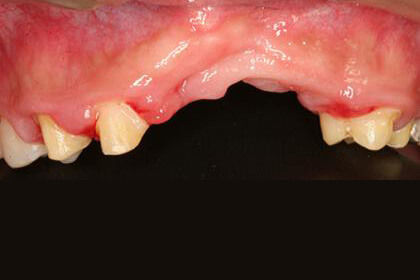

インプラント治療/骨造成

Before

After

基礎データ 23歳・男性

治療期間 3年

治療費 250万円

主な治療 抜歯・歯列矯正・骨造成(GBR)・インプラント埋入・クラウンブリッジ補綴・歯肉形成

治療計画

重度垂直的欠損に対して、厚みと固さのある歯肉(角化歯肉)の量を増やし、歯槽堤の幅・高さを増大する手法(インターポジショナルグラフト)で対応します。

不足している角化歯肉の幅の上皮を含む結合組織を移植して、フラップを唇側にずらして移植された組織と重なるように固定することで、既存の組織が理想の審美領域に移動します。これにより角化歯肉の量が増加し、唇側に歯肉の幅と高さを増やすことができます。